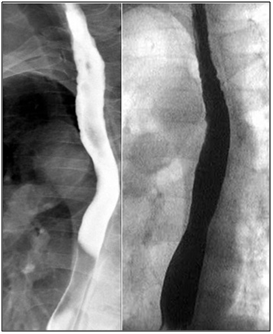

Symptoms recurred despite compliance with therapy and EGD two months later showed persistent LA Class D esophagitis without histologic evidence of opportunistic infection. A bariums wallow showed a tight 3cm long, 4 mm diameter stricture in the same location (Figure 2). Given the unusually refractory nature and mid-esophageal location of his circumferential esophagitis and stricture and no histologic evidence of Barrett’s, opportunists, or neoplasia, MMF was suspected to be the culprit. His MMF was discontinued and azathioprine was substituted. He was re-dilated to 12 mm using a through the scope (TTS) balloon. Barium swallow (Figure 3) at 3-month follow-up showed no evidence of esophagitis or stricture and PPI therapy was discontinued without symptomatic recurrence. At 2.5 year follow up he continues to be symptom free off of PPI therapy.

Figure 2 Barium swallow in November 2013 showed a tight 3 cm long, 4 mm diameter stricture in the lower third of the esophagus.

Figure 3 Normal barium swallow at 3 month follow-up.